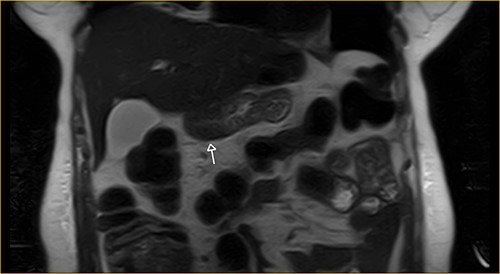

Laboratory examination showed anemia. An excluded stomach distention and parietal thickening of the pylorus and antrum were identified during abdominal computed tomography (CT) and magnetic resonance imaging (Figs 1–4). Thoracic CT was normal.

Coronal section on contrast magnetic resonance showing excluded stomach distention with parietal thickening of the pylorus and antrum (arrow).